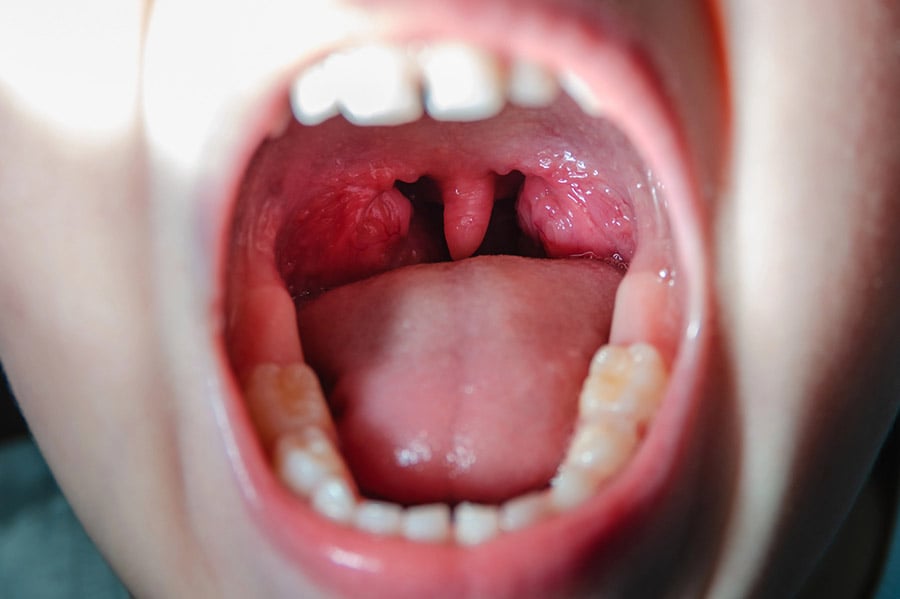

Най-често бактерията се свързва със скарлатина и ангина, а обикновено инфекциите започват в гърлото. Най-ясният симптом е зачервен обрив на точки. Лека инфекция от Streptococcus pyogenes е фарингит и импетиго (кожна инфекция с червени петна, мехури и корички, обикновено при деца).

Еризипел (наричана още “червен вятър”) и инфекциозен целулит (не бива да се бърка с козметичното натрупване на мазнини под кожата) са други болести, причинени от мултиплициране на Streptococcus pyogenes в дълбоките слоеве на кожата. Бактерията може да се развива и във фасцията (съединителна тъкан, която обгръща мускули и други структури в тялото), като там причинява некротизиращ фасциит (животозастрашаващо, ако не се лекува).